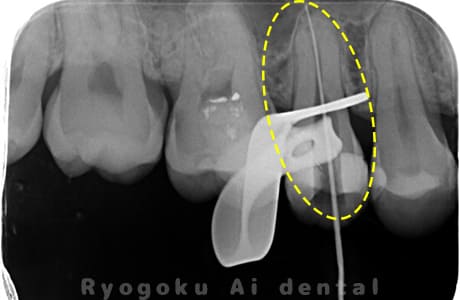

Case02

- 慢性根尖性歯周炎

- 治療期間

-

- マイクロエンド

- 治療費用

噛むと痛みが出る、とのことで来院した患者様です。他院での根管治療を終えてましたが、根尖病変を認めるため、マイクロエンドを行いました。